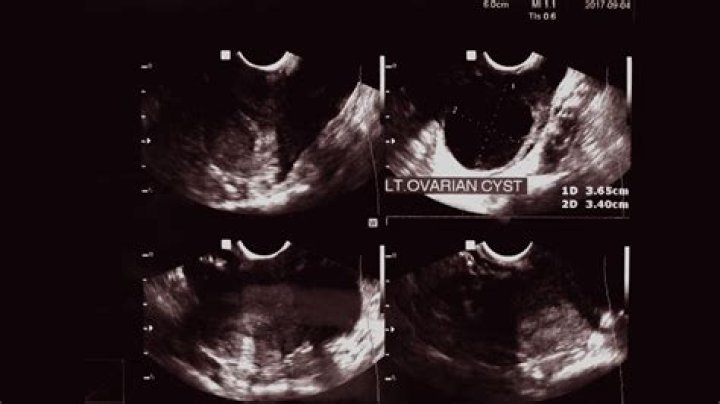

Do ovarian cysts cause smelly discharge?

Other symptoms include: pain during sex. painful urination. vaginal discharge that may be smelly.